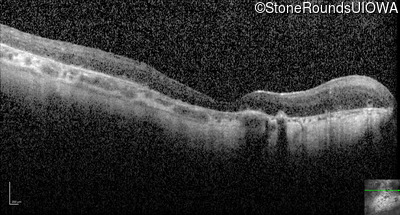

Optical Coherence Tomography - Right - Light Perception

Exemplar / OCT Stack

Optical Coherence Tomography - Left - Light Perception